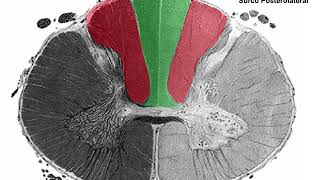

They emerge from the anterior horn of the spinal cord, remember that in the spinal cord video I explained that these anterior roots emerged through a groove called the anterolateral groove and that it was precisely the place where the lateral white cord and the anterior white cord were limited, that is very important. Then we will have the posterior roots that are the complete opposite of the previous ones, why? Because these posterior roots come out of the posterior horn, see that it is the counterpart of the anterior horn that originated the previous ones and these posterior roots bring sensitive information, that is, information that reaches the spinal cord with information, which is why it is called that its fibers are of the afferent type, so efferent is the one that they bring or those that come out through the anterior root, efferent or sensitive is the one that arrives through the posterior root, you see that each root is made up of a group of rootlets.

let's say more and more divergent when they get closer to the cord and when they move away from the cord as they get closer to the spinal nerve itself as such they become more convergent between them, that is important for you to know, these posterior roots are Your part, remember that I told you that they came out of a groove called the lateral dorsal groove, which, by the way, was the groove that delimited the lateral white cord from the posterior white cord, very good, now let's talk about what these are like. origins of these spinal roots, remember then what I told you since each root as such, which this would be, is made up of fibers, rootlets that are converging as they move further and further away from the spinal cord to form a single root, okay? Here we see it a little better between a cross section at the thoracic level, I know it is thoracic because you see the lungs here, I see the thoracic aorta too, we are going to see that the origin of each let's say spinal root varies according to the segment in which it is located.

? The dural sac is everything that is inside this envelope on the outside that is the dura mater, that is, everything that is here, see that the anterior root, which is this, once they emerge from the anterolateral sulcus, will continue laterally and posteriorly or towards posterolateral as I put here, for its part the posterior root, I know that this is the posterior one because the dilation it is giving, the posterior root when it is inside the dural sac that emerges through the dorsolateral sulcus is directed anteriorly and laterally , towards lateral, that is, towards anterolateral, important, the anterior towards posterior and the posterior towards anterior, at this level they continue to be enveloped by the same pia mater which is this membrane that is covering the spinal cord; So at that level it is surrounded by nothing more than the pia mater, remember that this space that is here between the pia mater and the arachnoid is the subarachnoid space, so once they always look to the side they pierce the arachnoid, see how that are perforating the arachnoid, anyway here we can see the arachnoid in blue, in red the pia mater and here the pia mater wraps around the spinal nerve when it is at the request of the subarachnoid space which is this blue, what you see Here in green is the dural membrane, that is, the dura mater as such, notice that once it is looking for the external part, it finishes passing to the arachnoid and begins to perforate this green membrane that is the dura mater, then each spinal root is going to pierce the dura mater through an independent hole, that is, each hole allows a single nerve to pass through as such, at this level it is enveloped by both the pia mater and the arachnoid and in turn begins to gain the envelope of the dura mater, it has the triple envelope At this level, pious mother, arachnoid and now also dura madre, when it comes out of the rural sac we are going to see that these roots are directed through this space that is the intervertebral foramen, okay? conjunction hole and both roots join and form the spinal nerve itself but this is formed outside the dural sac, in order for them to finish coming out they have to go through this operculum, which is this ligament called the fibrous operculum, we see it from here We see that the union of the roots is done very outside the dural sac, notice that it is quite outside and in addition they do it after they leave the intervertebral foramen, this is important so that you can see here you see how the roots are surrounded by the arachnoid that It is transparent and then wrapped by the hard mother and finishes making another wrap that in fact continues to wrap around the entire spinal nerve because it practically fuses with the perineurium, one thing that I took advantage of in this image and I show you is the dentate ligament, this The dentate ligament is found from above in the first medullary segments and ends more or less at the level of t12 and l1.